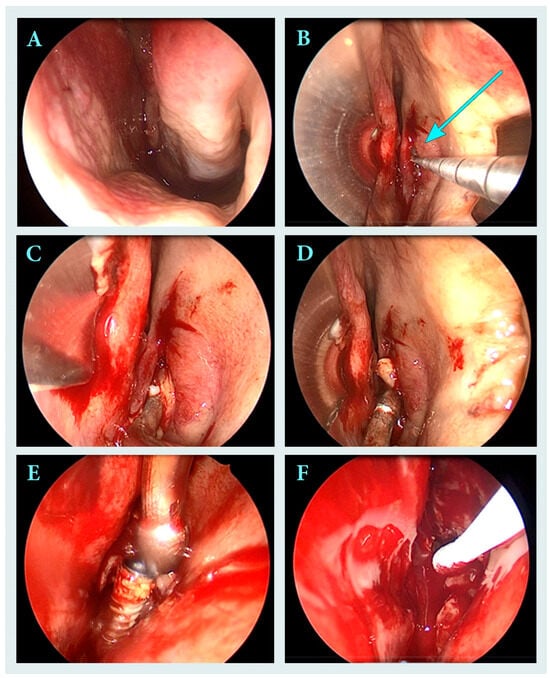

Iatrogenic maxillary sinusitis accounts for a significant proportion of unilateral sinus infections. This report describes a 36-year-old HIV-positive patient with Serratia marcescens chronic left maxillary sinusitis and ethmoiditis caused by migration of a dental implant into the maxillary sinus. The implant was successfully [...] Read more.

Iatrogenic maxillary sinusitis accounts for a significant proportion of unilateral sinus infections. This report describes a 36-year-old HIV-positive patient with Serratia marcescens chronic left maxillary sinusitis and ethmoiditis caused by migration of a dental implant into the maxillary sinus. The implant was successfully removed endoscopically via functional endoscopic sinus surgery. Histopathological examination revealed polypoid mucosa with chronic inflammation, while microbiological culture grew Serratia marcescens, an uncommon and opportunistic pathogen. Targeted antibiotic therapy with trimethoprim/sulfamethoxazole was administered for 20 days. Six-month follow-up revealed complete remission without recurrence of sinusitis. Full article

Show Figures

Figure 1